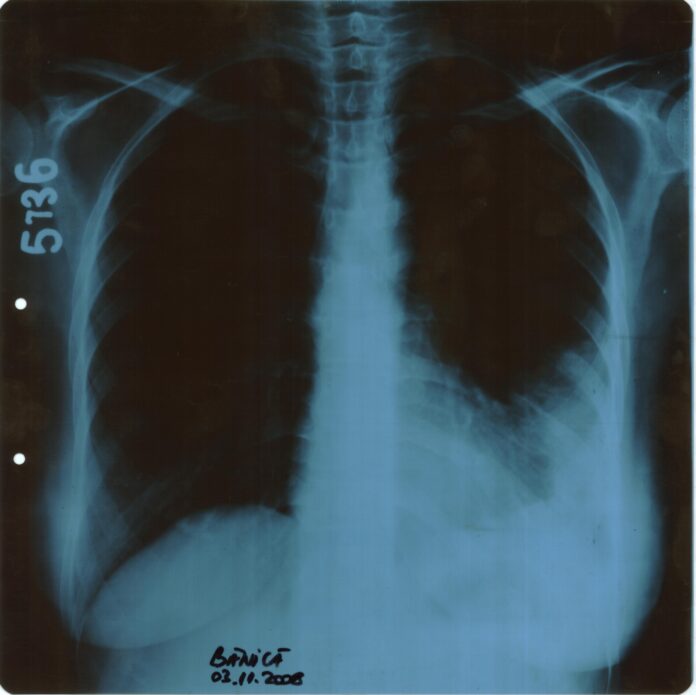

Într-un final, în data de 29.09.2023, m-am prezentat la UPU al Spitalului Clinic Județean de Urgență Cluj, unde am fost diagnosticată cu multiple tromboze, inclusiv TromboEmbolie Pulmonară – toate cauzate de lipsa tratamentului corespunzător cu anticoagulant, care trebuia prescris de medicii de pe Chirurgie, de la Câmpia Turzii.

După cum se știe, în literatura de specialitate, TromboEmbolia Pulmonară este o complicație extrem de periculoasă, care poate conduce la decesul pacientului. „Trombembolismul pulmonar reprezinta o complicatie grava a trombozei venoase profunde si se produce prin obstructia unei artere pulmonare datorata unui tromb de provenienta venoasa (cu formare la nivelul sistemului venos periferic), care determina ischemie acuta a tesutului pulmonar si insuficienta respiratorie acuta amenintatoare de viata.”[i]De asemenea, TROMBOZA COMPLETĂ OBSTRUCTIVĂ a venelor unui picior poate determina cangrenarea și, ulterior, amputarea piciorului.